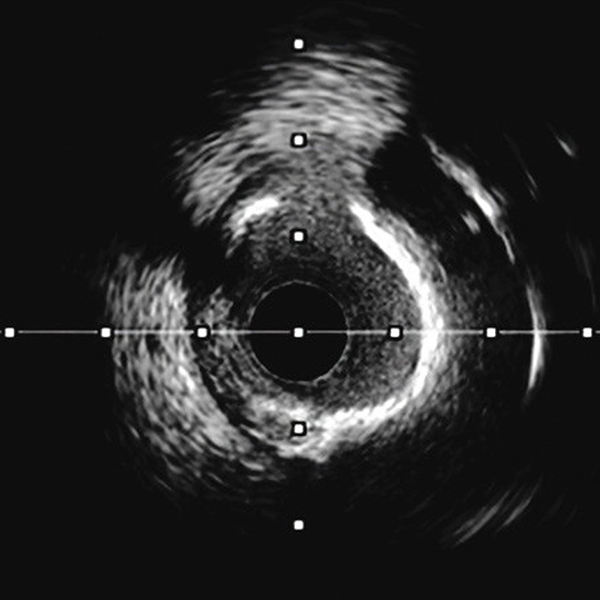

IVUS-guided assessment of lesion severity, characterizing plaque morphology